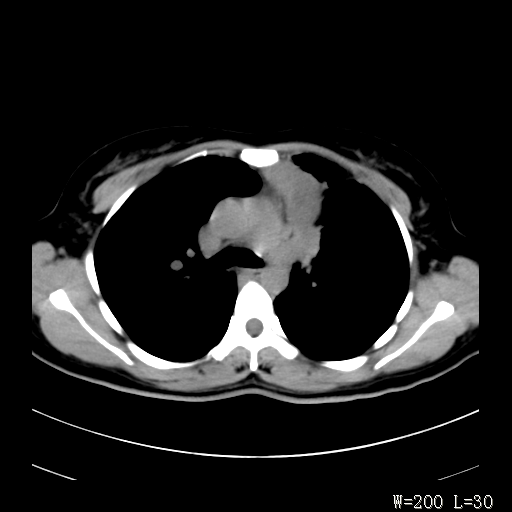

标题: CT27017:1、肺结核?2、永存左上腔静脉。 [打印本页]

标题: CT27017:1、肺结核?2、永存左上腔静脉。

女,32岁,自述肺结核治疗多年复查。

1)考虑左肺上叶肺脓肿,节段性肺不张。2)永存左上腔静脉。

1)考虑左肺上叶节段性肺不张。原因?2)永存左上腔静脉。

支持肺脓肿;还是双上腔静脉确切些吧,回流至冠状窦或右心房。

考虑左肺上叶胸腺瘤可能性大。肺不张/永存左上腔静脉

胸骨后偏左侧囊实性病灶,考虑胸腺瘤可能性大.

1、胸骨后偏左侧囊实性病灶,考虑胸腺瘤可能性大。2、永存左上腔静脉。